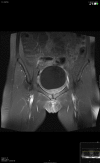

Osteomyelitis pubis is an infectious inflammation of the symphysis pubis and accounts for 2% of hematogenous osteomyelitis. This differs from osteitis pubis, a non-infectious inflammation of the pubic symphysis, generally caused by shear forces in young athletes. Both conditions present with similar symptoms and are usually differentiated on the basis of biopsy and/or culture. A case of osteomyelitis pubis is presented with a discussion of symphisis pubis anatomy, clinical and laboratory presentation, etiology and risk factors, and optimal imaging studies.